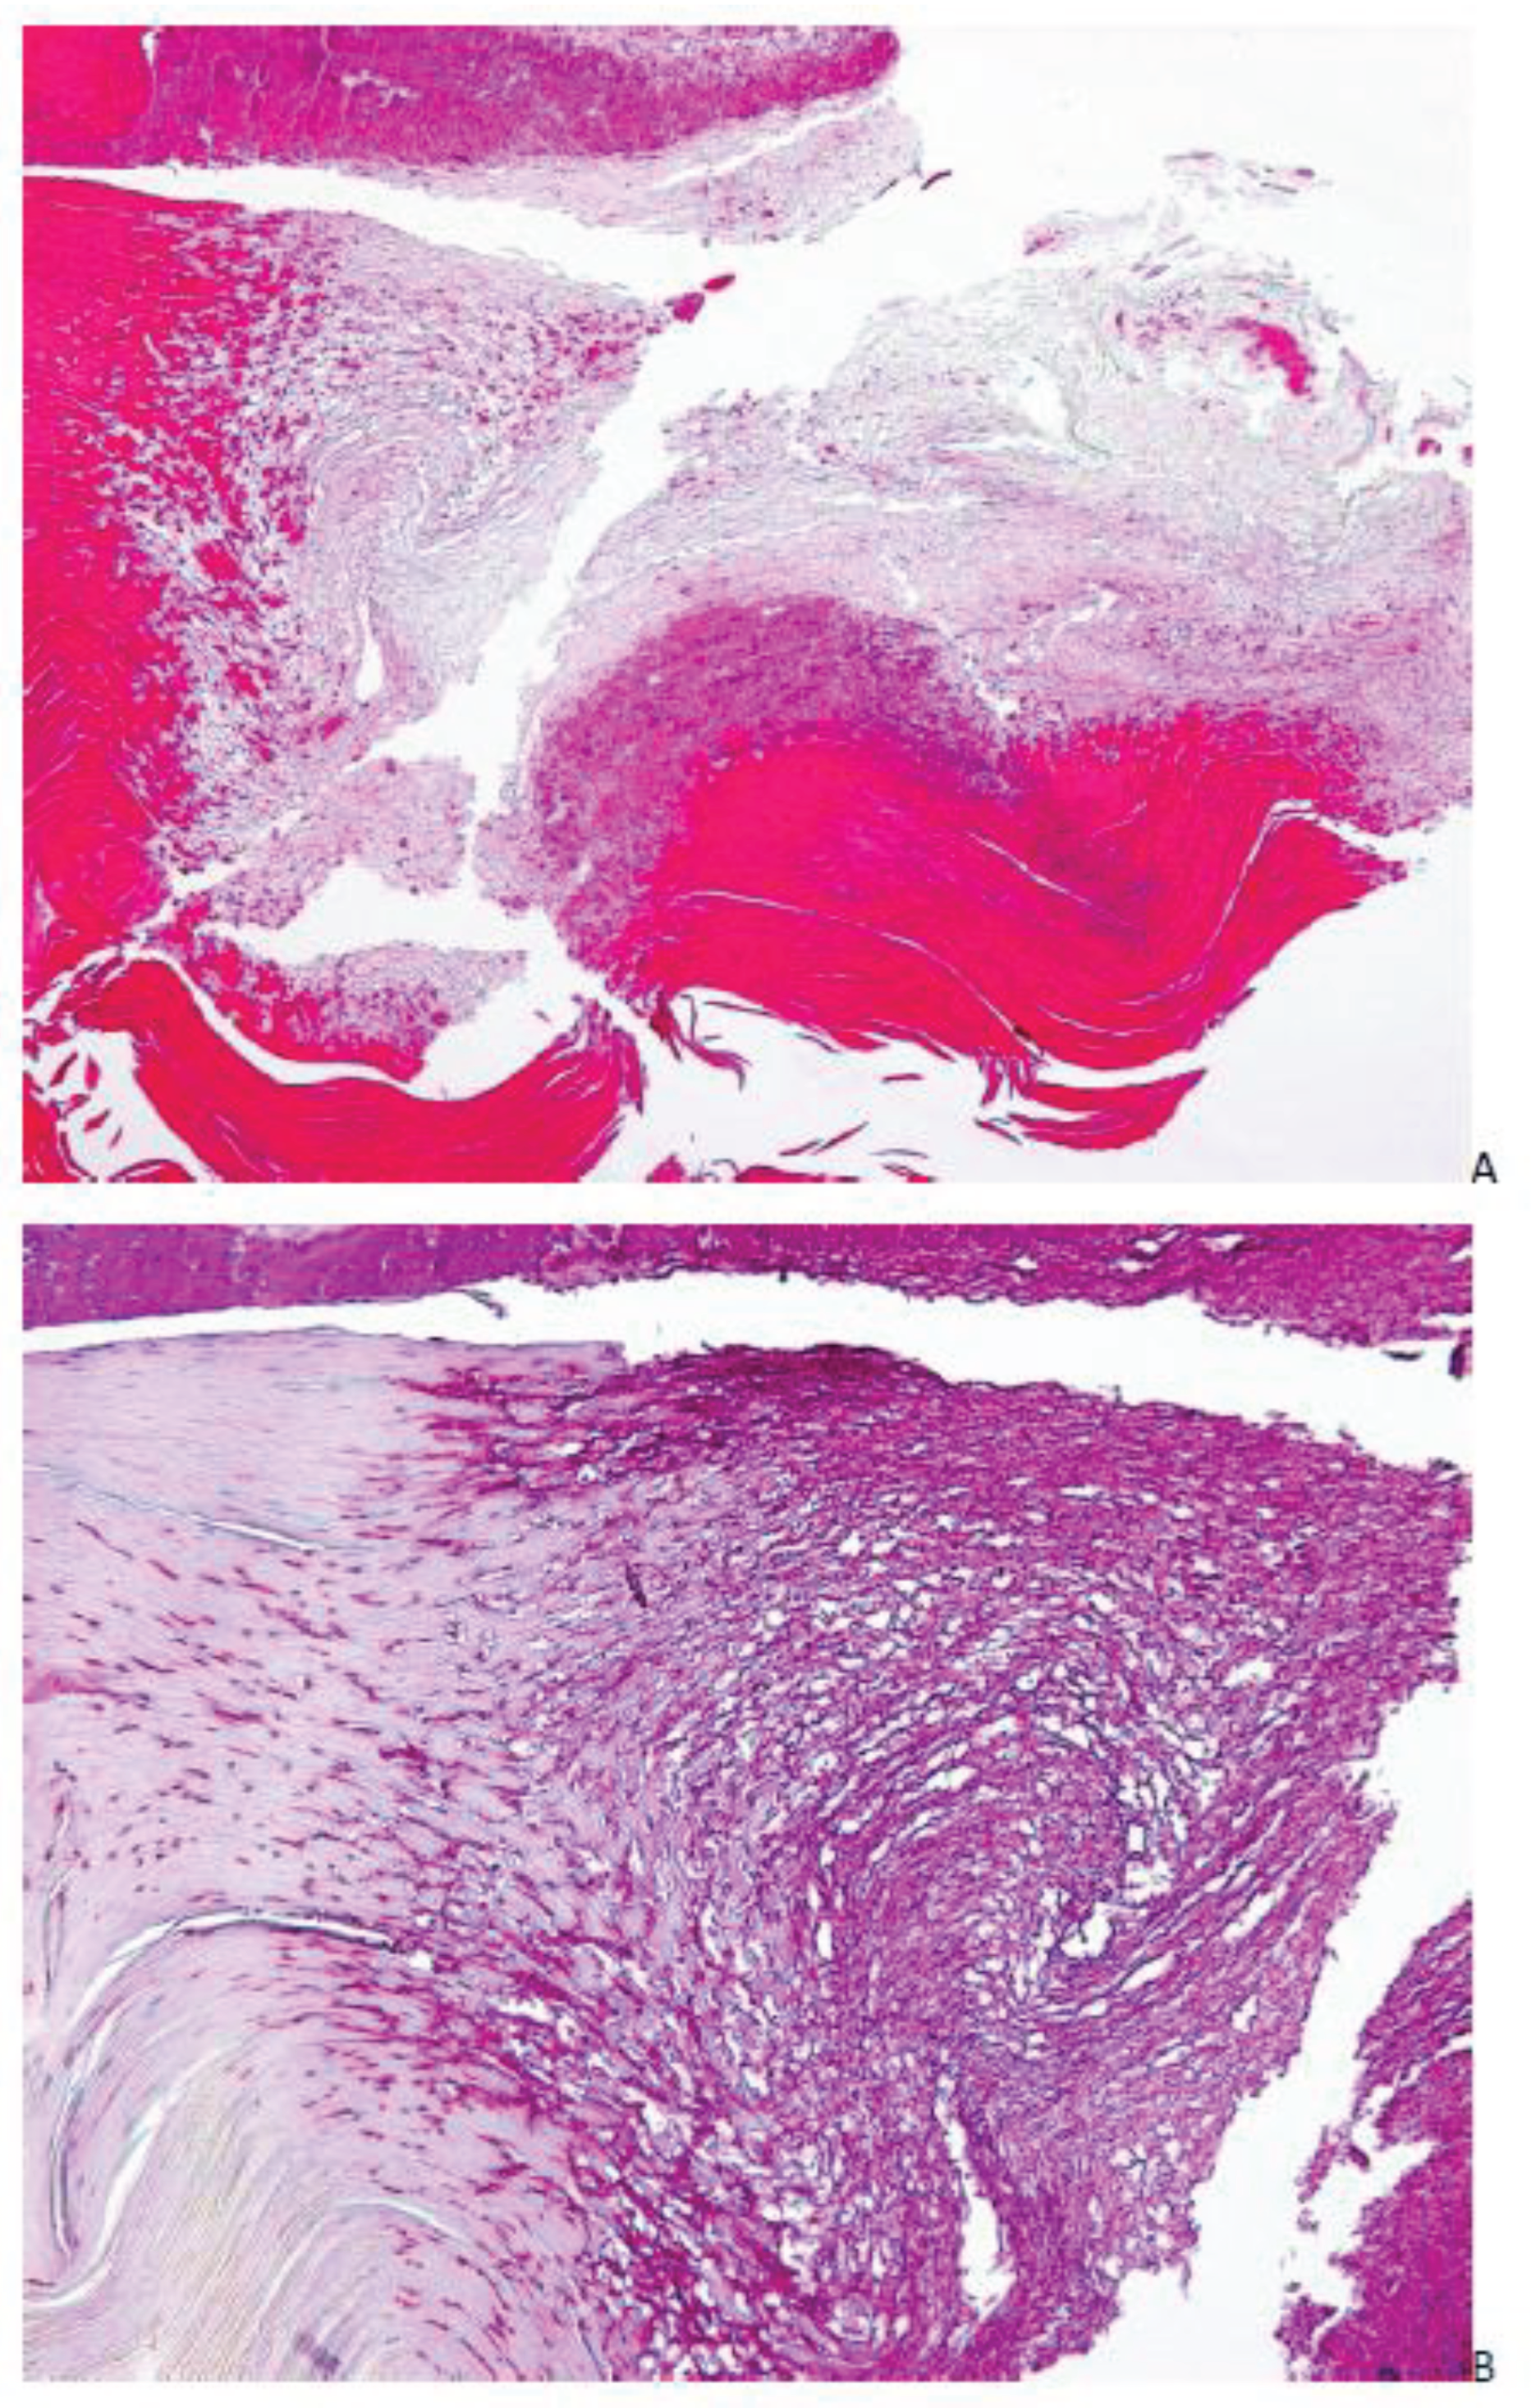

- Roberts DT, Evans EG. Subungual dermatophytoma complicating dermatophyte onychomycosis. Br J Dermatol. 1998;138(1):189-90. [CrossRef]

- Burkhart CN, Burkhart CG, Gupta AK. Dermatophytoma: Recalcitrance to treatment because of existence of fungal biofilm. J Am Acad Dermatol. 2002 Oct;47(4):629-31. [CrossRef]

- Markantonatou AM, Samaras K, Vyzantiadis TA. Dermatophytic biofilms: Characteristics, significance and treatment approaches. J Fungi (Basel). 2023;9(2):228. [CrossRef]